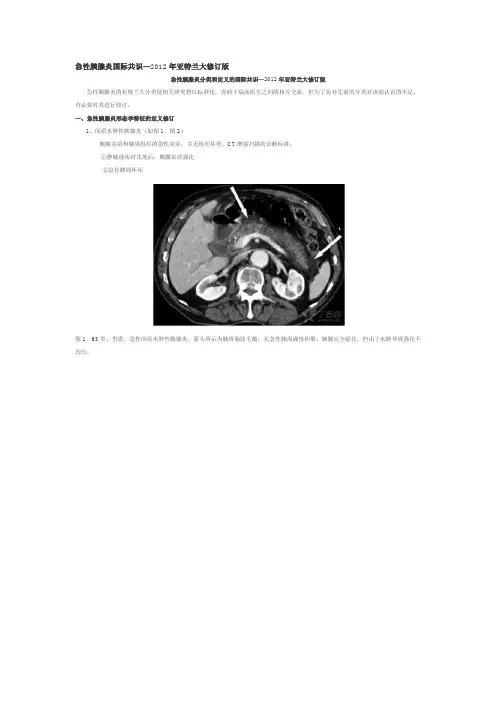

一、急性胰腺炎形态学特征的定义修订1、间质水肿性胰腺炎(如图1,图2)胰腺实质和胰周组织的急性炎症,并无组织坏死,CT增强扫描的诊断标准:①静脉使用对比剂后,胰腺实质强化②没有胰周坏死图1、63岁,男患,急性间质水肿性胰腺炎。

箭头所示为胰周脂肪毛糙,无急性胰周液体积聚;胰腺完全强化,但由于水肿导致强化不均匀。